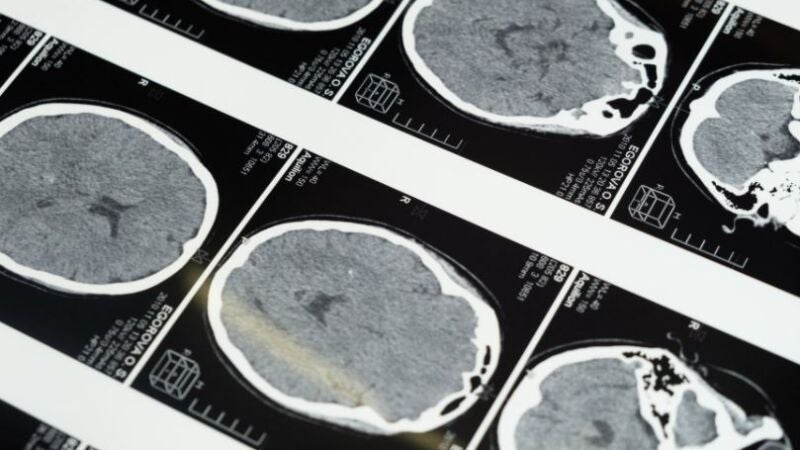

Atendiendo al tipo de alteración en la circulación hay ictus isquémicos y hemorrágicos. Sus causas son variadas, pudiendo ser una predisposición genética o patologías asociadas como diabetes, estrés o tabaquismo. Sin embargo, también puede ocurrir en personas que no presentan ninguno de estos factores de riesgo.